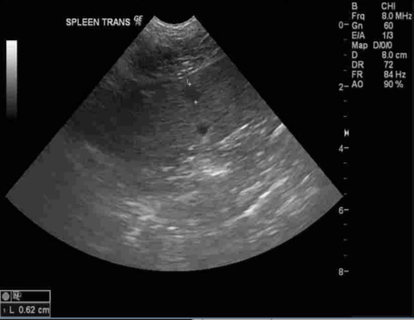

Abdominal ultrasound

- Hyperechoic liver (appears brighter than normal)

- Hyperechoic (brighter) small nodule in spleen, likely age related though neoplasia cannot be ruled out